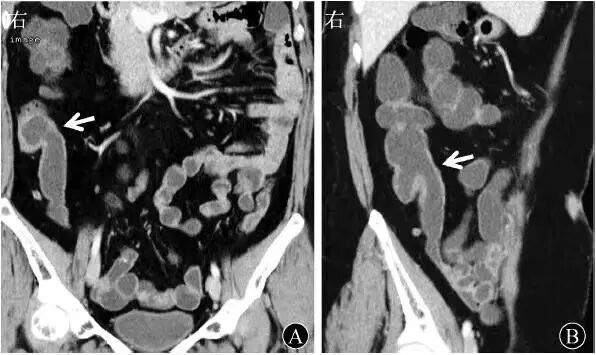

肠结核是由于结核菌侵犯肠管而引起的慢性特异性感染。好发部位以回盲部为多见,可占肠结核的85%~90%。

原发病灶的扩大,干酪坏死使肠管破坏,造成溃疡。同时该区域肠系膜淋巴结亦发生结核病变。肠结核的好发部位依次为回盲部、升结肠、回肠、空肠、阑尾、横结肠、降结肠、十二指肠、乙状结肠。

回盲部好发的原因有其解剖因素,回盲部淋巴组织最为丰富,结核菌从淋巴组织侵入肠壁形成结核病灶;也有其生理因素,肠内容物在通过回盲部时由于生理潴留作用,停留时间较长使结核杆菌与肠粘膜接触时间增多。

30%~60%的肠结核可触及肿块,多见于右下腹,质较硬,相对固定,表面不平,形态多样,有压痛。

腹块常由结核性肉芽肿、纤维组织、病变增厚的肠袢与周围组织粘连或肿大的肠系膜淋巴结组成。